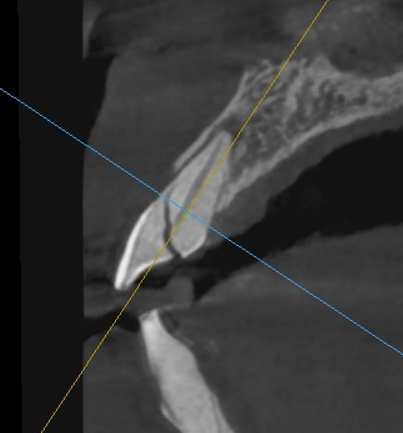

계획된 위치에 정확하게 임플란트 뿌리(픽스쳐)를 식립했습니다.

앞니 잇몸뼈는 얇기 때문에 뼈의 양과 형태를 고려하여 아주 신중하게 접근해야 합니다.

사전에 계획한 대로 임플란트가 아주 잘 위치한 모습입니다.